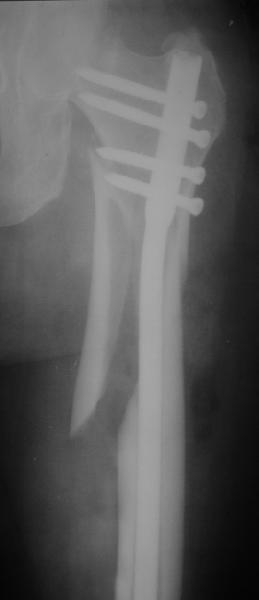

В частности, на проксимальном конце сделано еще одно дополнительное статическое отверстие. Можно ввести в проксимальном отделе 4 винта, из них 3 статические (2 в круглые отверстия и 1 по нижнему краю овального). Картинки в приложении. На дистальном конце стержня тоже кое-что улучшено. Спрашивайте в аптеках, как говорится. Выпускается предприятием "ЦИТО" (Москва), то есть это малобюджетное решение.

Конечно, мы не синтезируем остеопорозые вертельные переломы согласно прилагаемому примеру, винты 6 мм вырежутся. Но у более молодых при хорошем качестве кости такие или подобные гвозди с поперечным расположением винтов вполне применимы для меж- и подвертельных переломов.

Это было года 2,5 назад, мы тогда еще уточняли возможности шинирования с угловой стабильностью гвоздем с поперечным расположением винтов при переломах проксимального отдела бедра. Пациенту не пришлось приобретать намного более дорогой рекон или проксимальный гвоздь. В приложении еще несколько примеров применения того гвоздя при высоких переломах бедра, в том числе с более латеральной точкой входа. Гвоздь изгибаем для этого.